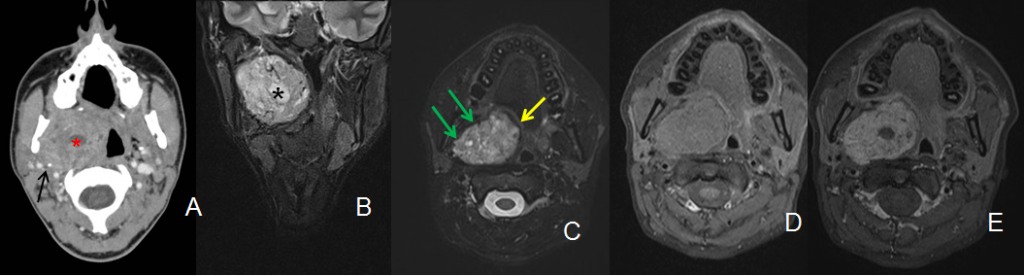

A. Tc de cuello con contraste. B. RM STIR coronal. C. RX T2 fat sat axial. D y E. RM T1 fat sat sin y con contraste i.v.

Masa bien delimitada de contornos lobulados localizada en el espacio parafaríngeo preestíleo derecho: medial a la cara interna del músculo pterigoideo medial (flechas verdes) y anterior a la apófisis estiloides (flecha negra) que se encuentra desplazada posteriormente. La masa es heterogénea por la presencia de áreas de degeneración necróticoquística (asterisco). Presenta una cápsula hipointensa en secuencias potenciadas en T2 (flecha amarilla). Tras la administración de contraste se realza de forma moderada.